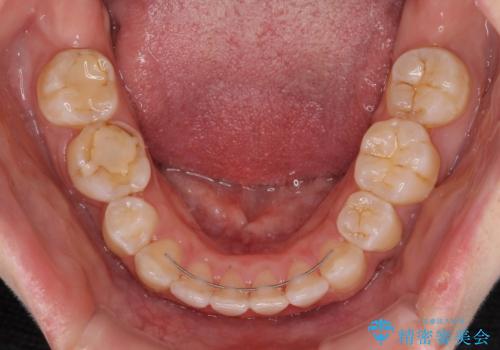

前に出ている上顎 抜歯矯正で唇を閉じやすく

第二小臼歯抜歯はイレギュラーな治療手段であり、治療期間が延びる傾向にありますが、舌のトレーニングをしっかりと行ってくださり、2年弱という非常に短い期間で理想的な仕上がりを達成することができました。